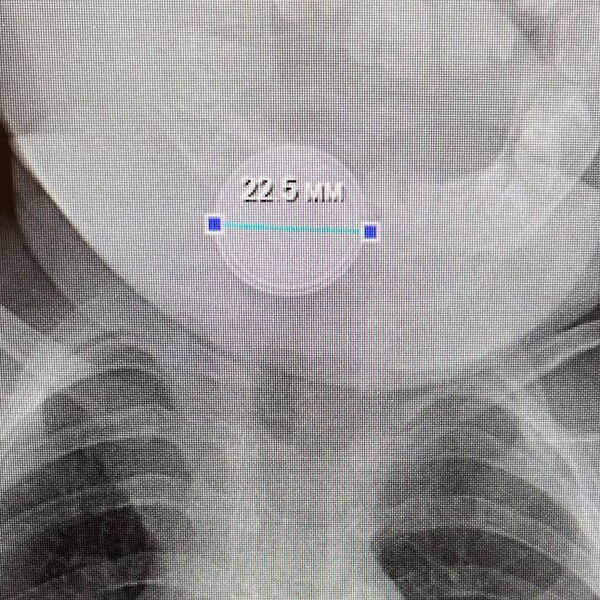

В приемное отделение больницы села Казанское был доставлен десятиместный младенец, ребенок с трудом дышал, сильно кашлял и вел себя беспокойно. В ходе обследования медики обнаружили в желудке маленького пациента инородное тело — круглую батарейку.